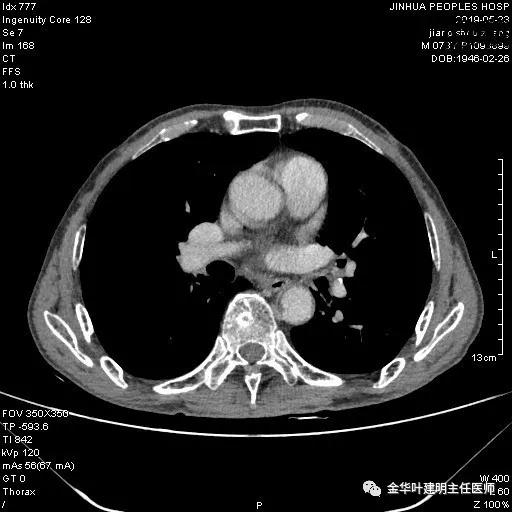

术前检查冠脉CT示:左冠前降支近段多发钙化斑块伴管腔重度狭窄(约85%),建议DSA检查。但追问病史以往平时无胸痛或胸闷症状,运动试验提示可疑阳性(上斜型压低),活动后胸闷气闭症状不明显,既往否认高血压、糖尿病。所以经过心内科会诊讨论,认为还是可以进行手术。术前冠状动脉CT示: